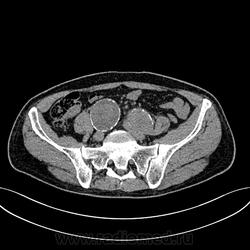

Пациент лежит в кардиологии. Прислали на аортографию. 2 врача УЗИ несколько разошлись в диагнозах: одна видит тромбированную аневризму брюшной аорты, другая - тромбоз нижней полой вены.

А мы получили вот такие красивые картинки.

Шикарно! Тромбированная аневризма инфраренального отдела (над бифуркацией), бифуркации и общих подвздошных артерий, синдром Лериша справа.

И еще маленькая аневризмочка наружной подвздошной слева. Честно говоря, меня больше всего впечатлили коллатерали, благодаря которым клинически он вообще не соответствует исследованию. Конечности теплые, пульсация слабая, но как-то прослеживается...